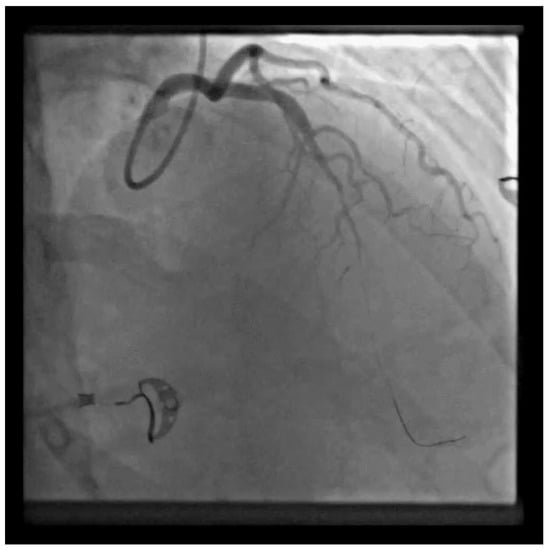

Catheterization of the coronary artery showed spontaneous type 2B coronary artery dissection (SCAD) with thrombolysis in myocardial infarction (TIMI) with flow grade 2 of the left anterior descendent (LAD) coronary artery located in the medial distal segments (blue arrow) where stenosis extends to the end of the vessel (Video S1). SCAD is defined as a nonatherosclerotic or iatrogenic separation of the coronary arterial tunics with a non-traumatic cause, secondary to vasa vasorum hemorrhage or intimal tear, which creates a false lumen, coronary compression, and downstream myocardial ischemia [1]. The primarily affected demographic groups are young-to-middle-aged women [1]. This can sometimes be an unrecognized condition. SCAD can cause acute myocardial infarction (AMI) and sudden cardiac death [2,3]. A previously healthy 42-year-old woman presented to the emergency department with a complaint of gradually squeezing chest pain in rest which lasted for 2.5 h. She had also noticed vomitus and an increased blood pressure value of of 170/120 mmHg. She was admitted to the Cardiology Department at the University Clinical Center of Serbia. No previous diseases were found in her medical history. She underwent five normal deliveries and one spontaneous abortion. The last delivery was eight years ago. She did not use any hormonal therapy. No special family history was reported. In admission to the Coronary Care Unit, she was hemodynamically stable and without signs of heart failure. Her blood pressure was 120/80 mmHg and her heart rate was 98 bpm.